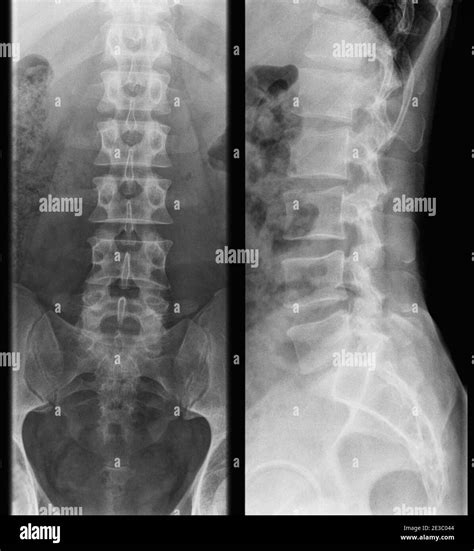

Lumbar Spine Normal X Ray

Understanding the structure of your lower back is essential when dealing with persistent pain or discomfort. When you visit a healthcare provider for lower back issues, one of the first diagnostic tools they often utilize is a Lumbar Spine Normal X Ray. This imaging technique provides a detailed view of the five vertebrae in your lower back, helping physicians rule out fractures, severe alignment issues, or significant degenerative changes. While an X-ray is considered a foundational diagnostic test, understanding what a "normal" result entails can help demystify the process and better prepare you for your medical consultation.

A lumbar spine X-ray is a non-invasive medical imaging test that uses a small amount of radiation to capture pictures of the lower back. It is typically the first line of imaging requested for patients presenting with chronic lower back pain, trauma, or suspected scoliosis. The primary purpose of this exam is to visualize the bony structures, including the vertebral bodies, the intervertebral disc spaces, the facet joints, and the sacroiliac joints.

When a radiologist reviews a Lumbar Spine Normal X Ray, they are checking for structural integrity. They are essentially confirming that the bones are aligned correctly, there are no breaks, and there are no glaring signs of tumors or infections affecting the bone tissue. It is important to note that while X-rays are excellent for looking at bones, they are limited in their ability to show soft tissues like nerves, muscles, or herniated discs.

Key Components of a Normal Lumbar Spine X-Ray

To determine if an X-ray is normal, radiologists look for specific markers of health within the lumbar region. A report will generally indicate that the bones are in their proper place and that no acute pathologies are present. Below are the key components identified in a standard, healthy report:

• Vertebral Alignment: The vertebrae should be stacked in a smooth, gentle curve known as the lumbar lordosis.

• Disc Spaces: These are the gaps between the vertebrae. In a healthy spine, these spaces should be uniform in height, suggesting that the intervertebral discs are adequately hydrated and intact.

• Bone Density: The bones should appear white and dense, without signs of thinning (osteopenia) or unusual spots that could indicate disease.

• Facet Joints: These joints, which connect the vertebrae, should appear smooth with clear boundaries, free from significant arthritic changes.

• No Fractures or Dislocations: The most crucial aspect of a normal report is the absence of any bony breaks or slippage (spondylolisthesis).